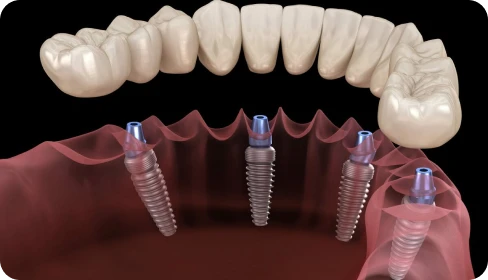

Con la técnica de carga inmediata colocamos una prótesis fija provisional justo después de la cirugía (o dentro de las primeras 48 horas).

Meses después, cuando los implantes ya han cicatrizado, se sustituye la prótesis provisional por la definitiva.

Sí. Esa es la esencia de la carga inmediata.

Sales de la clínica con una prótesis fija provisional, sin tener que esperar meses con un hueco o una dentadura removible.

Desde el primer día podrás masticar alimentos blandos.

Cuando los implantes cicatrizan por completo (unos meses después), la prótesis definitiva te permite volver a comer con total comodidad.